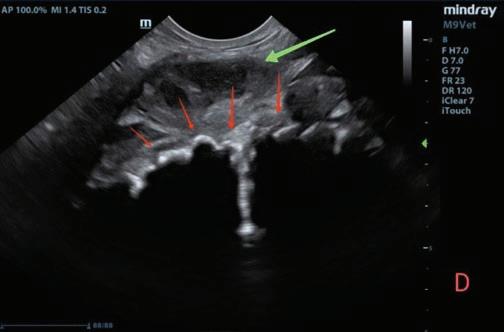

mitral (EDVM), presentando engrosamiento, prolapso e insuficiencia valvular, dilatación del atrio izquierdo (AI/AO=1,9) y leve aumento de las dimensiones diastólicas del ventrículo izquierdo normalizado al peso del paciente (NLVDD=1,7). Las presiones de llenado intracardiacas se estimaron como normales, ya que el flujo transmitral presentó un patrón de relajación anómala y la velocidad pico de E fue de 0,8 m/s. En función de estos hallazgos se confirmó el diagnóstico de enfermedad degenerativa valvular mitral con cardiomegalia izquierda y sin hallazgos compatibles con insuficiencia cardiaca congestiva, por lo tanto en estadio ACVIM B2. En las vistas ecocardiográficas paraesternal derecha de 4 cámaras y apical izquierda de 4 cámaras se visualizó una estructura redondeada y anecógena de 15 mm, con flujo sanguíneo en Doppler color, adyacente al corazón (Fig. 2). Este hallazgo es compatible con dilatación aneurismática de las estructuras vasculares o las cavidades cardiacas, si bien no

Figura 2. Ecocardiografía. (A) Vista apical izquierda de 4 cámaras optimizada para ADD. Engrosamiento de la válvula mitral (VM), dilatación moderada de atrio izquierdo (AI) y ventrículo izquierdo (VI). Estructura redondeada y anecógena de 15 mm con flujo sanguíneo (AAD), adyacente al corazón. AD: atrio derecho. (B) Vista paraesternal derecha de 4 cámaras optimizada para el atrio izquierdo. Estructura redondeada y anecógena (AAD) asociada al corazón. AD: atrio derecho.